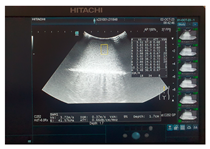

- Criteria 4: optimal characteristics for ultrasound—how optimal/not optimal is the model for ultrasound examination;

- Criteria 5: optimal characteristics for elastography—how optimal/not optimal is the model for ultrasound elastography;

| Ultrasound |  |  |  |

| Ultrasound |  |  |  |

| Ultrasound |  |  |  |

| Ultrasound |  |  |  |

| Ultrasound |  |  |  |

| Ultrasound |  |  |  |